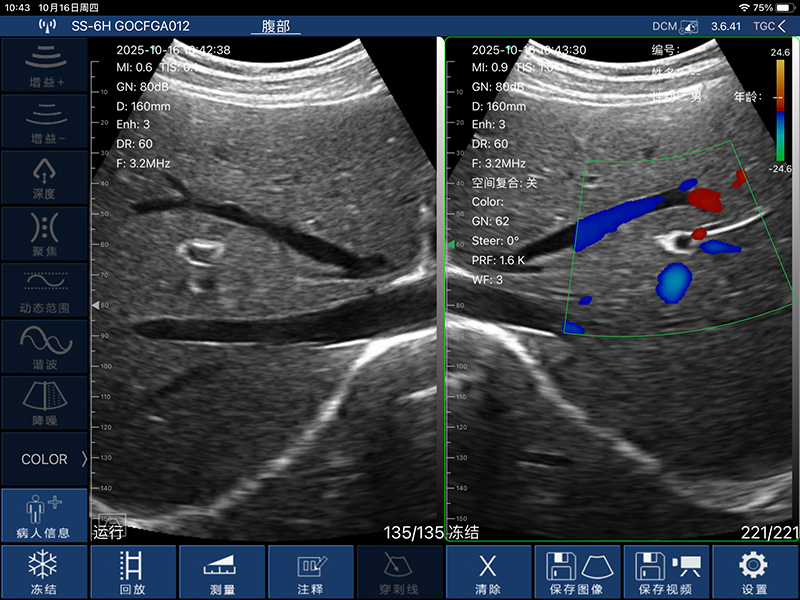

• 扫描方式:电子阵列扫描

• 探头频率:3.2/5.0MHz

• 扫描深度:90/160/220/305mm,可调

• 显示模式:B、B/M、Color、PW、PDI